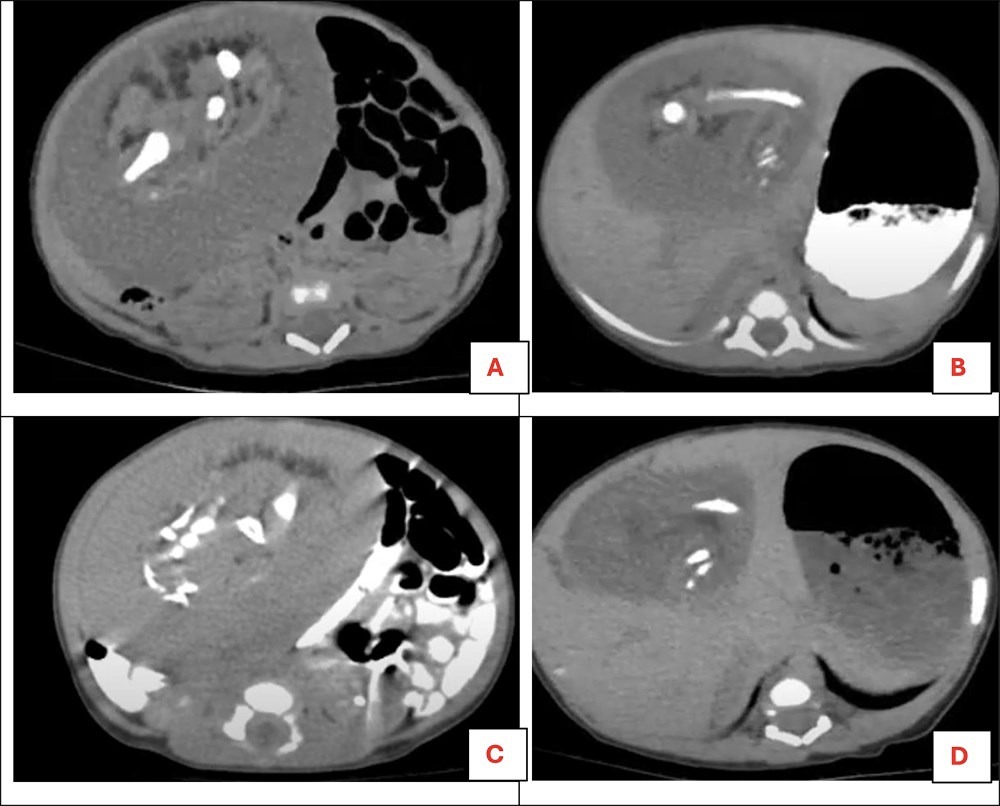

The baby, just 11 days old, was admitted to the hospital after her stomach began to swell unusually. Concerned by her growing abdominal size, doctors conducted a 4D scan, which revealed an 8×6 cm mass with a “soft to firm consistency” and an “irregular surface” that did not move when she breathed.

Further investigation showed that the lump was connected to a large artery, leading doctors to identify it as a case of “fetus in fetu” — a rare medical anomaly where a malformed parasitic twin develops inside the body of its sibling.

A team of surgeons at the Mansoura University Paediatric Unit performed a laparotomy (surgical incision into the abdomen) and discovered the mass located near the baby’s liver.